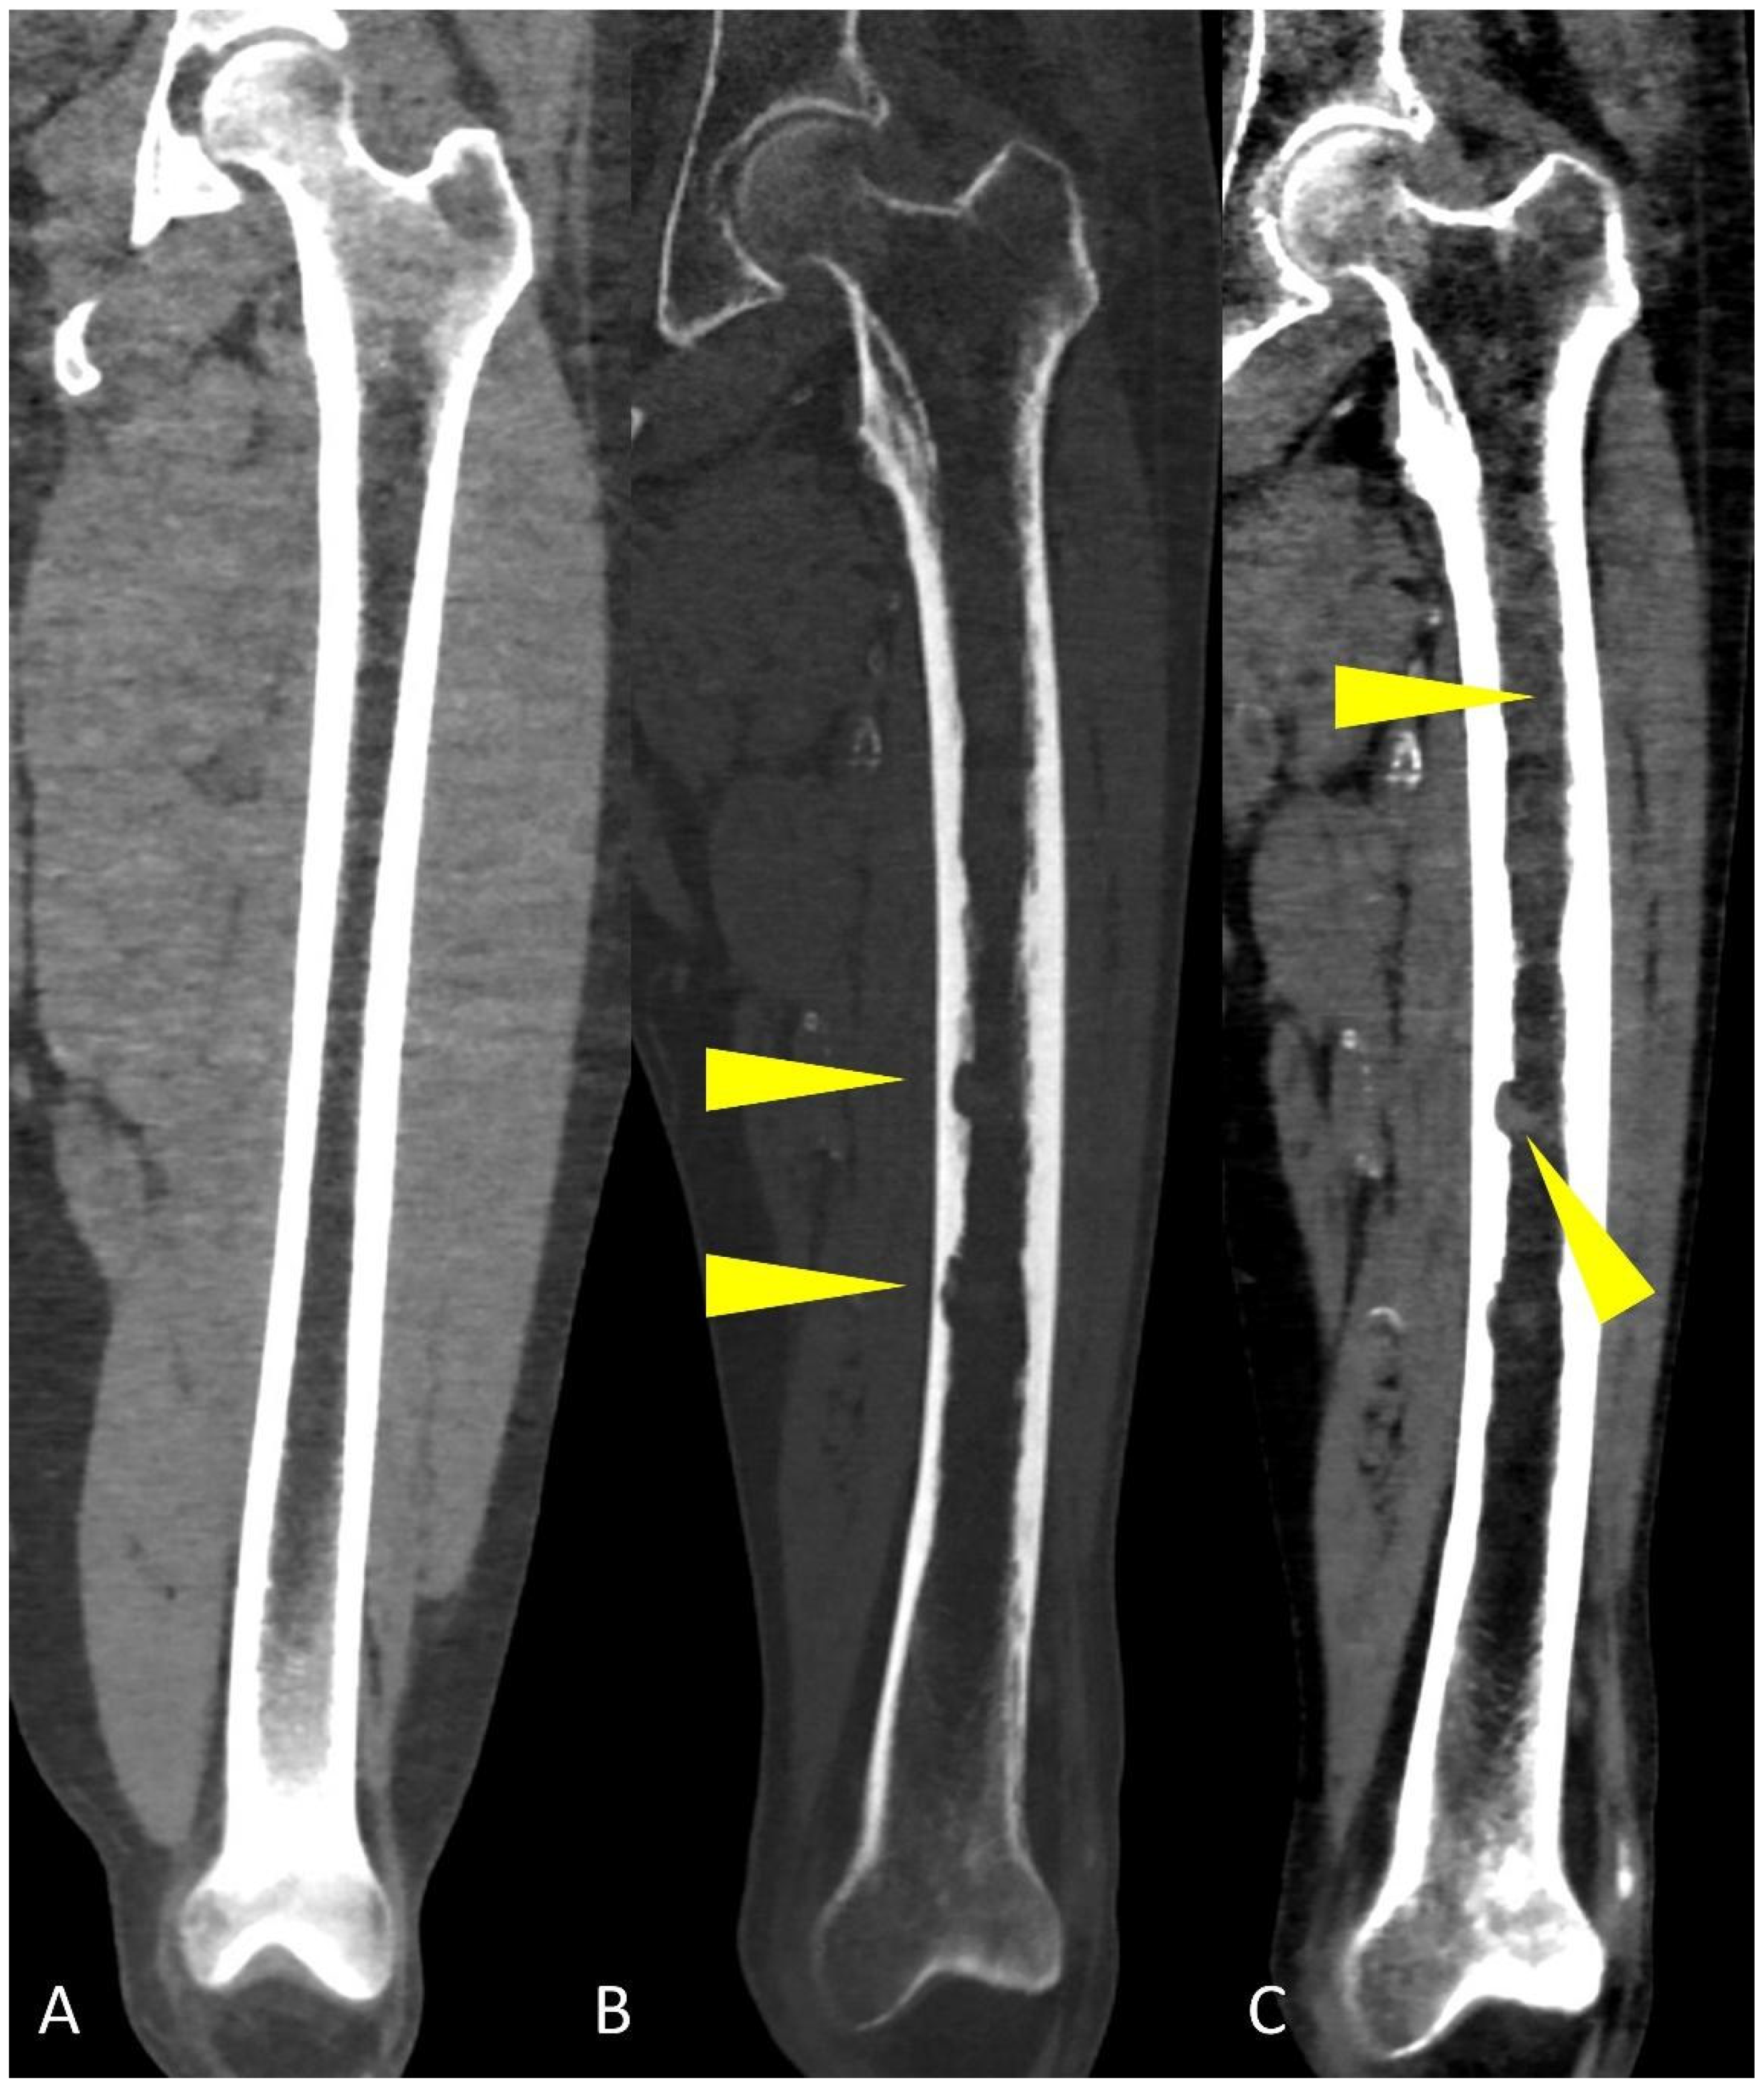

Figure 7.

Coronal CT reconstruction images of the femoral bone showing: (A) regular aspect of bone marrow without osteolytic lesions, endosteal scalloping and pathological deposits; (B) “bone” algorithm reconstruction, used to evaluate osteolytic lesions and endosteal scalloping (yellow arrowheads); (C) “soft tissue” algorithm reconstruction used to assess focal and diffuse hyperdense deposits in the medullary cavities of long bones (yellow arrowheads).